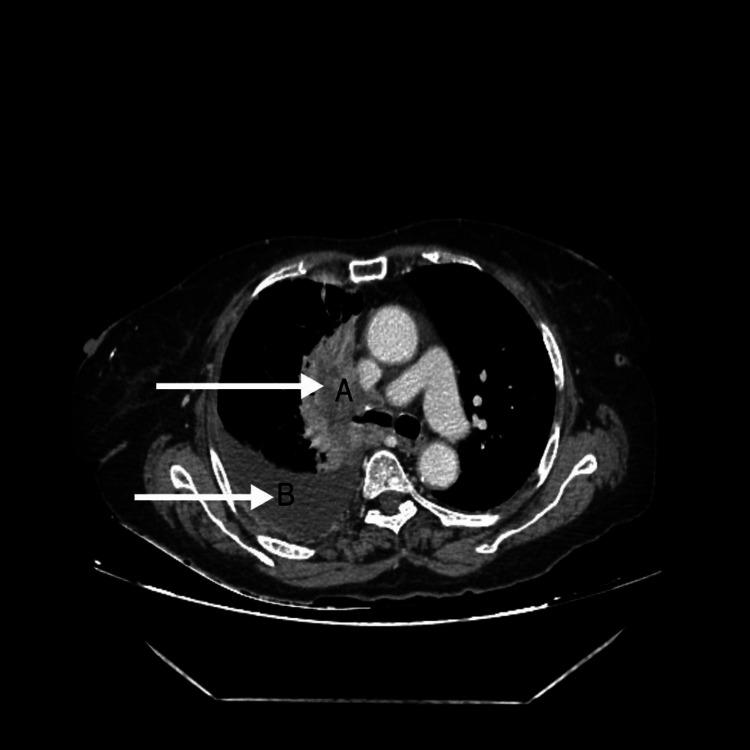

原发性肺淋巴瘤(PPL)是一种累及肺部的罕见疾病,其特征为淋巴样细胞的异常克隆性生长。PPL患者可能无症状,或表现出如咳嗽、发热、胸部不适和呼吸急促等模糊的临床症状。一些患者可能还存在潜在的免疫抑制或自身免疫性疾病。在流行地区,结核病更为常见且发病率更高,PPL常常会被误诊为结核病。此外,它们有共同的症状,如咳嗽、发热、疲劳、不明原因的体重减轻,且好发于上叶。因此,将PPL与其他常见肺部疾病进行鉴别诊断对于早期诊断和治疗至关重要。一般来说,小活检样本对于精确诊断和及时治疗必不可少。治疗选择包括化疗、放疗、免疫治疗和手术干预。在此,我们概述了一例最初表现为黑棘皮病,因呼吸道症状、胸腔积液和纵隔淋巴结肿大前来就诊的病例,最初被认为是结核性胸腔积液。除了临床放射学和实验室分析外,胸腔镜引导下活检和组织病理学检查为进一步诊断指明了方向。患者开始接受R-CHOP方案化疗。该病例表明,对于与弥漫性大B细胞淋巴瘤相关的副肿瘤综合征,需要多学科视角来进行明确和快速的诊断及管理。该讨论还强调了对副肿瘤综合征进行全面评估的必要性,因为它们在疾病的早期诊断和识别复发方面至关重要。